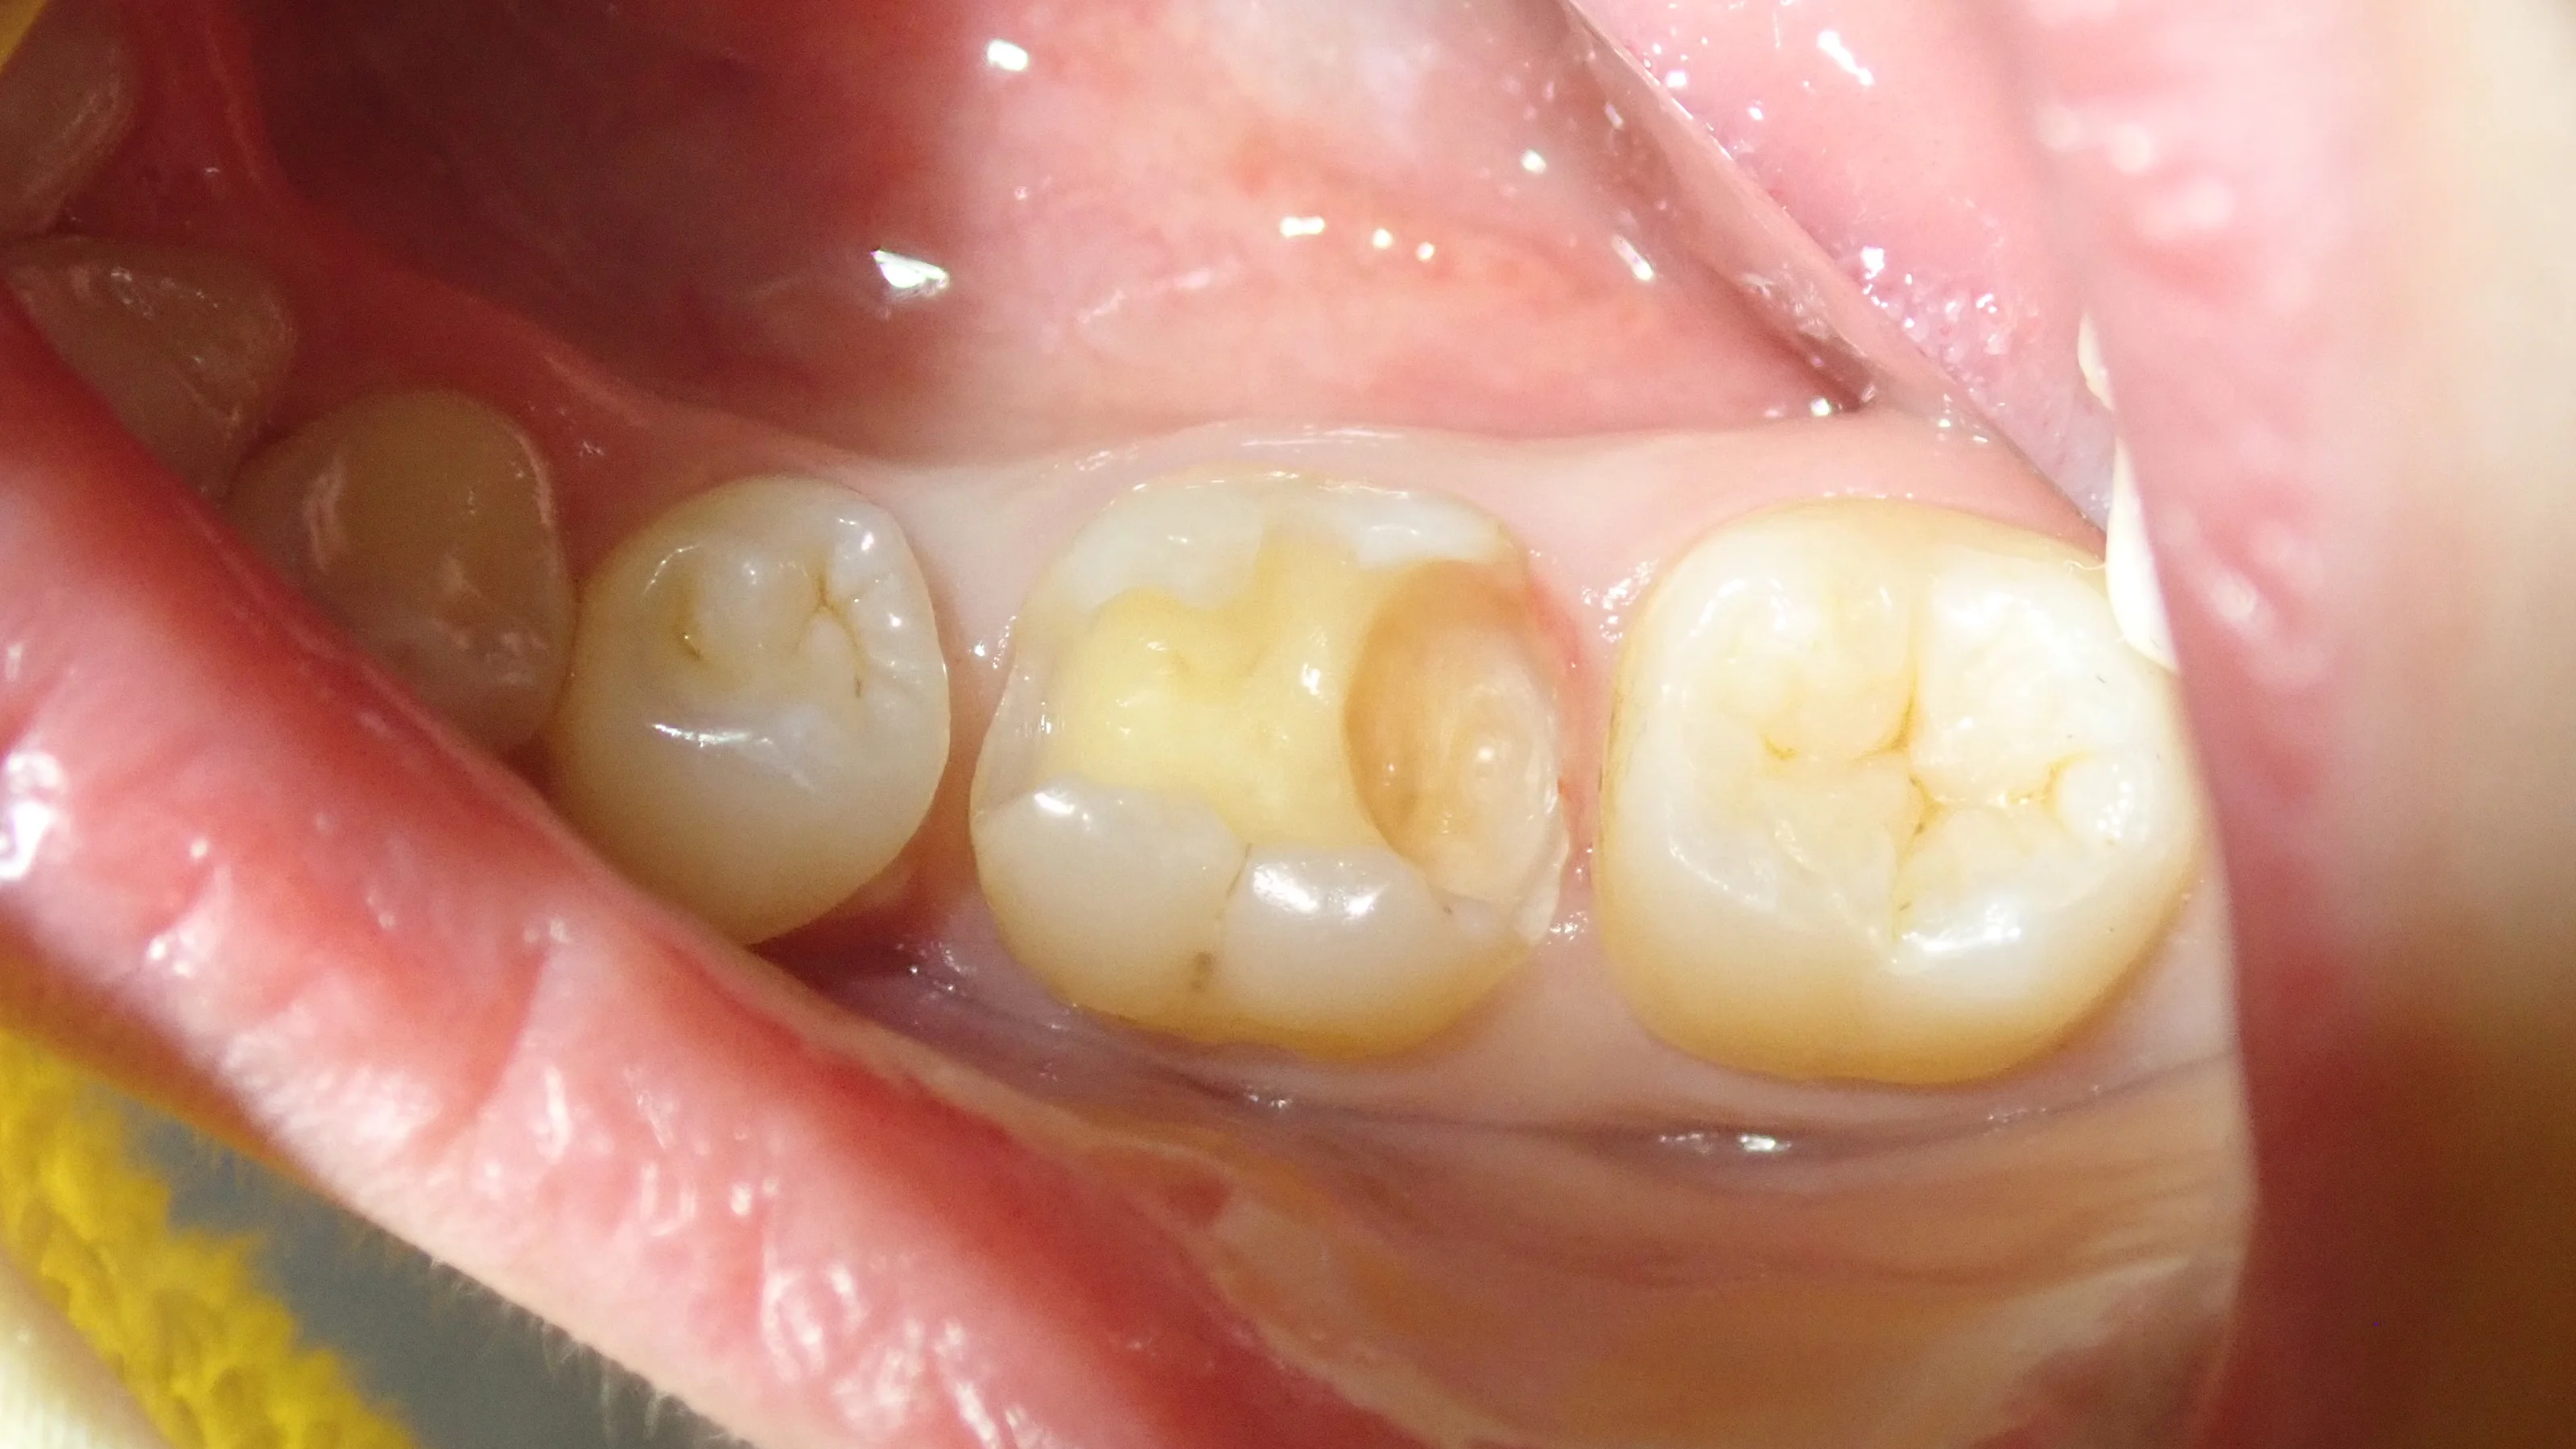

術前がこちら

手前の歯との間は矯正の後戻りによって隙間が開いている状況になっています。

金属を軽くとったのがこちらですね。

で、完全に虫歯を取り切ったらこうなりました。

後ろの歯との間が非常に深くなっています。

手前の歯との間についても、虫歯だったため、歯が少なくなってしまいました。

そして、詰め終わったのがこちら

スペースが非常に大きかったため、半ば無理矢理スペースを埋めました。